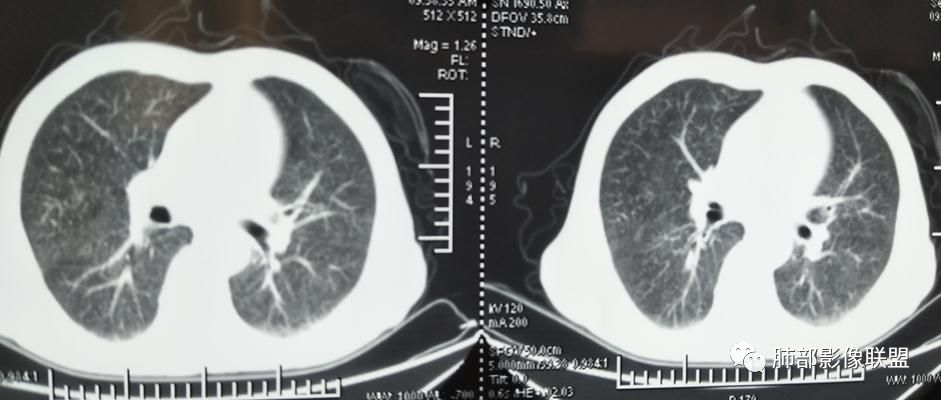

2019-10-20复查CT如下:

两肺弥漫性粟粒样结节伴左上肺小结节,呈三均匀分布,有结核的临床表现,支持血性播散性肺结核。

大小、分布均匀,边缘清楚

细小结节,弥漫,撒米粒样——血道来源

还是支持结核

血道来源的病灶,均匀、细微,而且部分有分支状,都符合粟粒型肺结核

10月20日的CT其实是抗痨治疗近1月复查的CT。患者来我院后抗痨治疗体温下降,症状明显好转。

急性血行播散型肺结核  两肺广泛分布粟粒大小的结节状密度增高影,具有大小均匀、分布均匀、密度均匀的典型“三均匀”特征,注意急性血播病灶非常小,一般粟粒影直径1~2mm。

病灶密集者出现肺外围血管影不清或减少。

发热初期肺部可缺乏典型影像学改变,1到2周后出现的广泛粟粒结节对诊断具有高度提示作用!